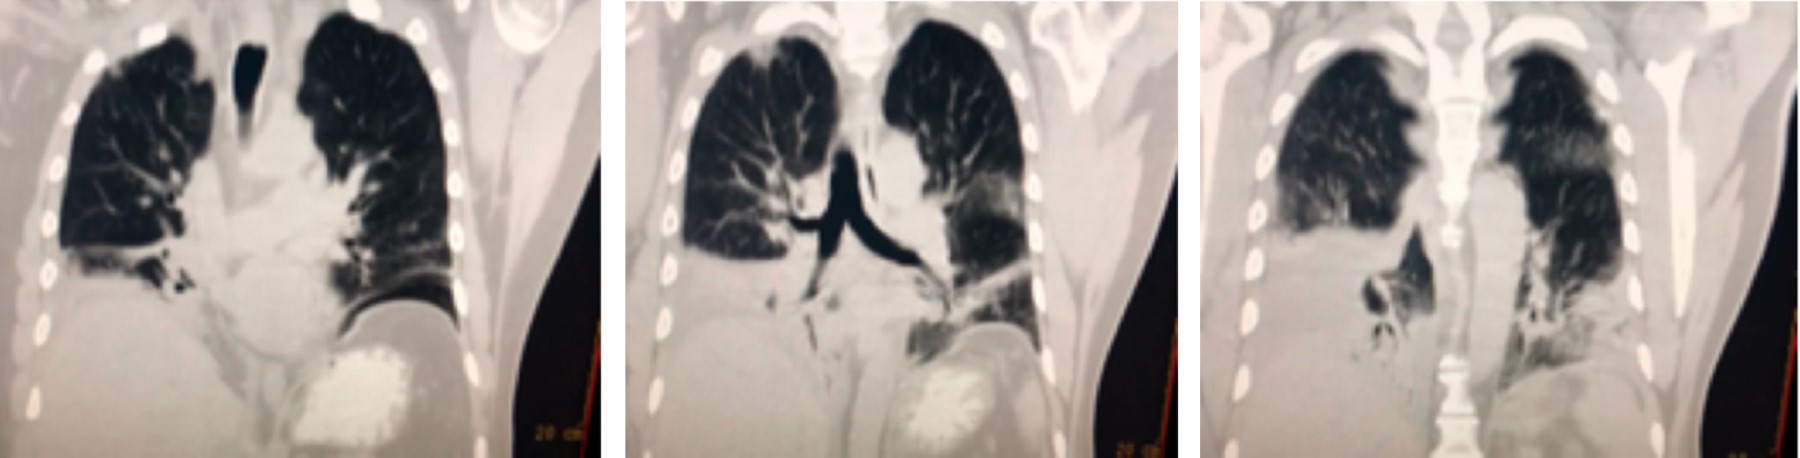

Posteriormente presenta datos de respuesta inflamatoria sistémica y elevación térmica asociándose en un inicio a sepsis abdominal y posteriormente a infección de catéter venoso central. Se realiza cambio del mismo sin mejoría reportando cultivo negativo, a lo cual se añaden estertores bésales y sibilancias. Al sexto día se integra clínicamente el diagnóstico de neumonía, mismo que es confirmado por radiografía de tórax (Figura 1), se solicita cultivo de secreción bronquial y se realiza tomografía toracoabdominal (Figura 2), que revela datos de neumonía asociada al ventilador y se agrega caspofungina al esquema antimicrobiano previo.

El paciente presenta mejoría relativa, se decide su extubación, un día posterior a esto persiste con deterioro clínico, se amplia cobertura de antimicrobianos para Staphylococcus aureus meticilino-resistente, se solicita nueva tomografía de tórax para control, en la cual persisten las zonas de consolidación en lóbulos inferiores, agregándose derrame pleural bilateral, el resto del estudio sin cambios significativos respecto al previo (Figura 3).

Por imagen muchas veces la radiografía no aporta grandes hallazgos, especialmente en estadios tempranos de la enfermedad, pero si éstos se visualizaran encontraríamos opacidades retículo nodulares de distribución difusa y con predominio del tipo peribroncovascular y en ocasiones distorsión de la arquitectura, por lo que una tomografía computarizada de alta resolución (TCAR) resultará más sensible, la cual muestra un patrón en vidrio deslustrado con nódulos centrolobulillares, en algunos casos patrón en mosaico con atrapamiento aéreo, con predominio en lóbulos inferiores y de distribución central; sólo en estadios crónicos se podría identificar un patrón en panal de abeja en una minoría de los casos.11,12

Figura 2